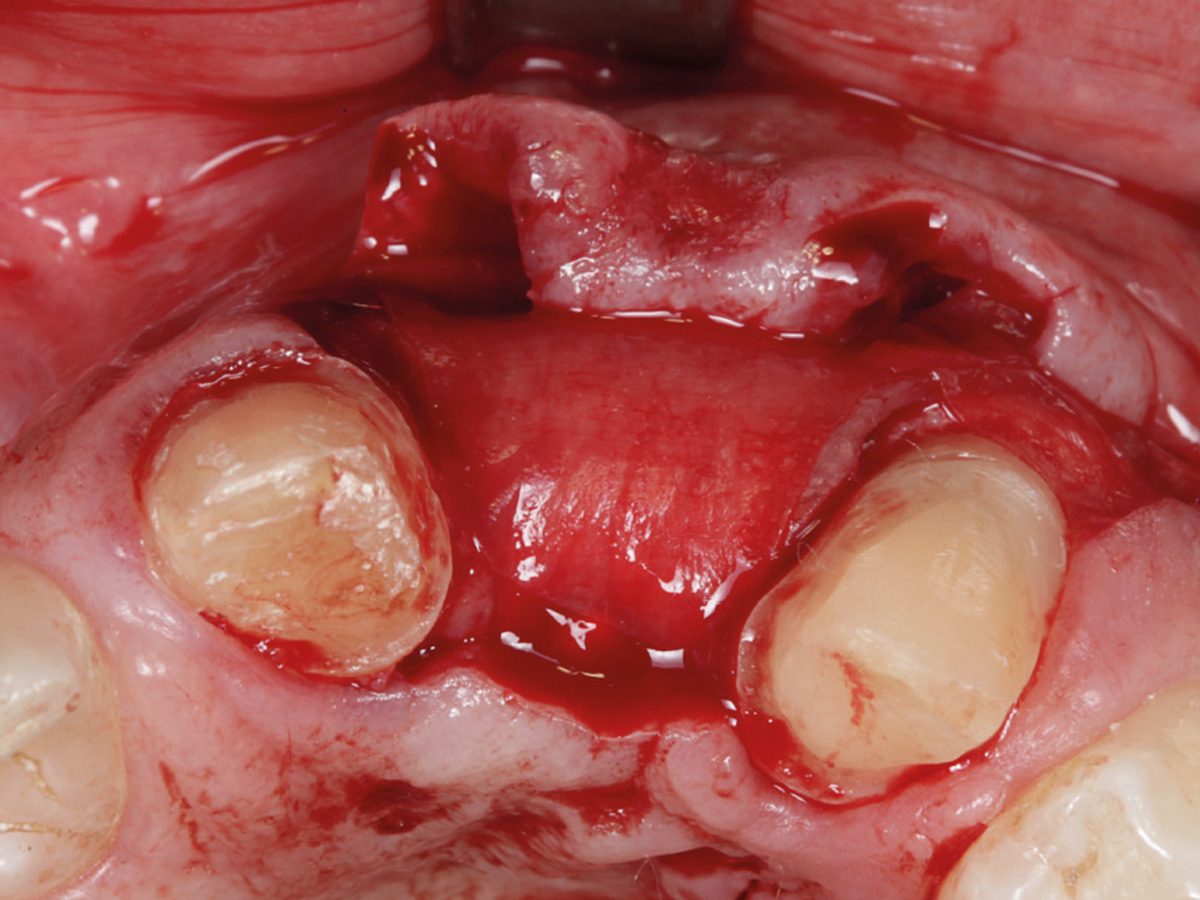

Abbildung 1

Horizontaler Alveolarkammdefekt, Einzelzahnimplantat soll eingesetzt werden.